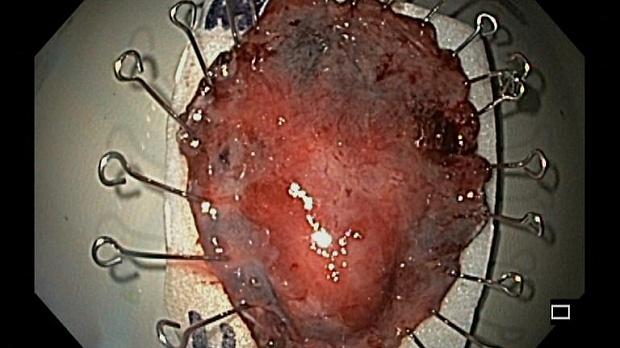

Иллюстрация №10: Рис. 8. Макроскопическое описание удаленного препарата: фрагмент слизистой оболочки, размерами 47 х 35 х 8 мм. Слизистая оболочка серо коричневого цвета, в 4 мм от проксимального края препарата определяется бугристое образование размерами 16 х 12 х 5 мм

Эндоскопическая операция была выполнена 26.09.2019г. в условиях эндотрахеального наркоза с использованием помпы для подачи воды в дополнительный канал эндоскопа GIF-H-180J (Олимпас, Япония) и инсуффляцией углекислого газа. Точечная маркировка слизистой оболочки (отступя от видимых краев опухоли 4-5 мм), циркулярный разрез слизистой оболочки вокруг опухоли (отступя от эндоскопических меток 3-4 мм) и диссекция подслизистого слоя выполнялись эндоскопическим ножом Triangle Knife (Олимпас, Япония). При создании тоннеля под опухолью в подслизистый слой вводился раствор гиалуроновой кислоты с индигокармином (рис. 7 a, b). В связи с хирургически измененной анатомией и ограниченным «малым желудочком» пространством во время операции возникали сложности в позиционировании и с навигацией. Это не изменило план операции; опухоль была удалена единым блоком. Гемостаз видимых сосудов в ложе удаленной опухоли был осуществлён коагуляционным зажимом «Coagrasper» (Олимпас, Япония). По окончании операции признаков перфорации, кровотечения не выявлено. Продолжительность операции составила 190 минут. Операционный препарат (40 х 50 мм) был извлечен, фиксирован на планшете и погружен в забуференный формалин (рис. 8).